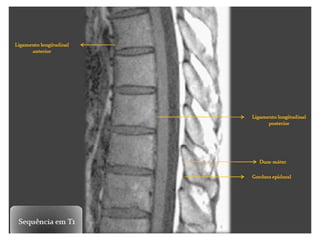

RM COLUNA VERTEBRAL